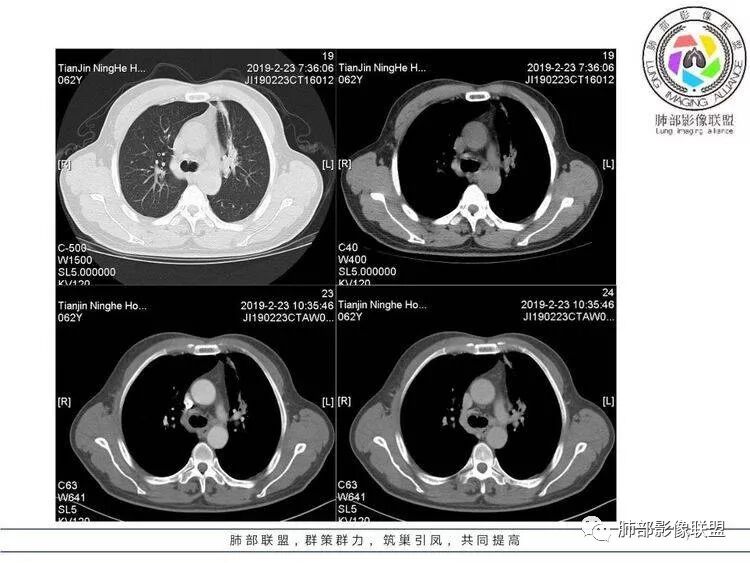

像雾像雨又像风,到底是什么?等你来判断。

病例资料

王秀仙:左肺上叶肿块,边缘平直收缩,周围可见长索条,轻度强化,密度不均可见低密度坏死,考虑结核。鉴别腺癌。Yiren  Sishui(厶水伊人):晨读:左肺上叶肿块,近胸膜侧光滑,提示符合淋巴回流病变,周围条索,符合肉芽肿性病变,环形强化,中心坏死,考虑结核可能luys:左肺上叶病变,沿支气管分布,边缘平直收缩,周围见长索条,轻度强化,伴边界可见低密度坏死灶。考虑特殊感染。灶内支气管中断,临床以咯血就诊,鉴别肿瘤。博麟:左上胸廓稍缩小,长条索病灶,冠状位似见支气管截断,坏死边界似乎欠清,猜个纤维条索基础上合并瘢痕癌红日东升:晨读:左上叶结块,前缘有粗大索条向前延伸,邻近前联合线明显左移,提示收缩明显。结块边缘平直、收缩;增强结块及索条明显强化,内血管走行自然,坏死灶周围似见三层结构;考虑炎性病变。wonderful:肿块实性边缘光滑  考虑良性病变 合并咯血 。结核或曲霉玫:左肺上叶不规则形软组织密度肿块影,边界清晰,期内密度不均匀,可见坏死,病灶向前呈条索状延伸,矢状位病灶形态欠规整,似有血管中断,考虑恶性病变可能,待除外结核?张帅:左肺上叶病变,病变周围平直,长毛刺,病灶内可见低密度区及支气管征,矢状位提示前段阻塞,病灶内气管不规则扩张,病灶周围有卫星灶,考虑良性病变:结核?我心飞翔:病灶边缘平直,中央可见坏死,周围磨玻璃边界欠清,考虑炎性病变张延军:左肺上叶尖后段肿块,边缘以平直为主,局部膨隆,内见片状坏死区,边界欠清,相应尖后段支气管闭塞,考虑占位并不张,腺癌?建议抗炎治疗后复查丽:左肺上叶病变,边缘平直,并可见长索条,增强后密度不均,可见坏死,首先考虑结核,但重建后支气管走形欠连续,似有截断,恶性待排毛勤香:左肺上叶病灶,边缘平直为主,周围索片影,增强强化不均匀,内有坏死,重建支气管走行欠规则,似有截断,老年男性,需排除恶性(鳞癌?)并阻塞性肺炎可能王萍:左肺上叶团片,大部分边缘平直、凹陷,周围见少许条片模糊影,增强内见坏死区,余区域较均质,其内支气管部分通畅,部分变窄。咯血病史,无发热,考虑肉芽肿性炎可能性大,结核或放线菌等,肿瘤待排THINKER:左上叶,占位,围绕尖后段支气管,U型凹丶平直,长索条,有轻强化及低密度,考虑良性的,首选OP,老年不发热丶咯血,鉴鳞癌、TB飞鹰行动:左肺病灶,有明显的收缩表现,增强后病灶内部可见低密度无强化区,病灶内支气管轻度扩张呈串珠状改变,支持炎性病变,结核可能性大。杨泽锋:支持炎性病变伴小脓腔形成,但不支持结核,因为病灶内可以可见血管影THINKER:问一下各位老师:这个给的强化,是肺动末期丶主动脉未期`延迟期?大雄:老年男性,左肺上叶前段条片状实变影伴周围长条索,境界清晰,边缘部分锐利光滑、部分毛糙,增强可见中央局部坏死,周围无强化区轻中度均匀强化,无钙化,无明显卫星灶,无胸膜明显牵拉凹陷。病灶整体收缩力有,张力不明显,肿瘤概率小。临床无明显急性感染症状,倾向于慢性增生性炎症,累及段支气管,引起了咯血。结核多见,但慢性结核肉芽肿一般强化没这么明显。OP不除外。老年男性如果有长期吸烟史,鳞癌不能完全排除,鳞癌的坏死强化都符合,鳞癌收缩力也不强,形态更是变化无常左手:老年男性,咯血,左肺上叶长条样结节,边缘见牵拉影,支气管堵塞,病灶内见坏死,坏死边缘偏清,考虑鳞癌,鉴别结核宇宙星空:支持恶性。鳞癌可能性大。支气管截断及空泡征

Shelia:考虑机化性肺炎伴小脓肿形成?炎性肌纤维母细胞瘤?鉴别癌食客:左肺上叶病灶,边缘平直,周围条片影,增强内见坏死区,内支气管部分通畅,咯血病史,无发热,考虑结核,肿瘤不除外。管洪林:左肺上叶尖后段病变,整体边缘平直,部分稍收缩,临近长索条影,胸膜缘可见轻度牵拉,增强后整体强化明显,其内可见低密度类圆形坏死区,边界清,首先考虑op并小脓肿形成,但部分层面显示小支气管受阻,是否层面原因?管洪林:若是支气管阻塞,鳞癌作为鉴别雪上一枝蒿(陈显静):他这个动脉期是不是不是很明显啊,觉得跟静脉期差不多,强化值也不好分辨?徐超:左肺上叶实变,边缘平直,周围无磨玻璃及卫星灶,病灶内坏死,强化后边界清楚,无壁结节,余病灶轻中度均匀强化(对比肌肉),增强后血管显影清楚自然,未见破坏边缘毛糙,血管旁条形无强化区(粘液?)整体符合炎性特点,炎性假瘤或op可能,伴小脓肿;结核放后面待排(结核病灶内血管完好,边缘清楚,且强化近中度,不是很合理,肉芽肿到也可以)。红日东升:平扫和强化窗宽窗位不一样良孑:左上实变,有平直及长毛刺,其内支气管牵拉性扩张,提示收缩力较强,无卫星灶,强化不支持TB,均匀强化,无分叶不支持鳞癌,影像上提示慢性进程,考虑OP并脓肿,鉴别炎肌母。

南边:应该是前段吧。前段的支气管怎么样?

南边:没有堵塞考虑啥?

南边:坏死如何?

南边:还是支持炎性吧